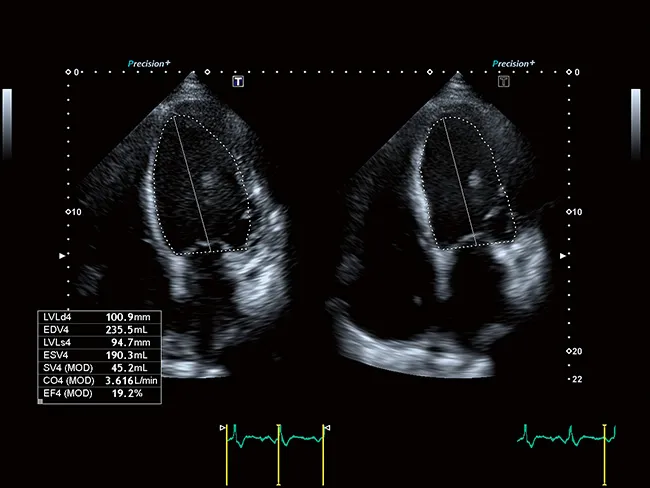

Aplio a450 – УЗИ-сканер экспертного уровня от широко известной среди экспертов УЗИ фирмы Canon (Toshiba). Аппарат является универсальным, особенно силен в онкологии и кардио исследованиях.

Точное количественное определение регионарной функции миокарда

Функциональная оценка лежит в основе визуализации сердечно-сосудистой системы. Предоставляя ценную дополнительную информацию в удобном для понимания визуальном, параметрическом или количественном формате, расширенные клинические функции Aplio помогут вам получить более быстрый и надежный диагностический результат.

Усовершенствованная технология отслеживания движения сердечной стенки Aplio обеспечивает немедленный визуальный и количественный доступ к глобальной и региональной статистике движения стенки миокарда.